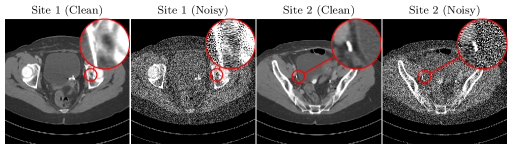

To assess the quality of reconstruction on medical data, we evaluate our method on simulated data from human abdomen CT scans from the low-dose CT Grand Challenge dataset [3]. This dataset contains full-dose reconstructions of 10 patients, consisting of a total of 237823782378 slices of 512×512512512512\times 512 pixels. Following [48], sinograms were computed from these reconstructions by projecting onto a fan-beam geometry. Noise was applied, corresponding to a photon count of 10,0001000010,000 incident photons per pixel. Reconstructions are shown in Figure 5.

Refer to caption

Figure 5: Original high-dose reconstructions of low-dose CT grand challenge (clean) and reconstructions with simulated noise (noisy).